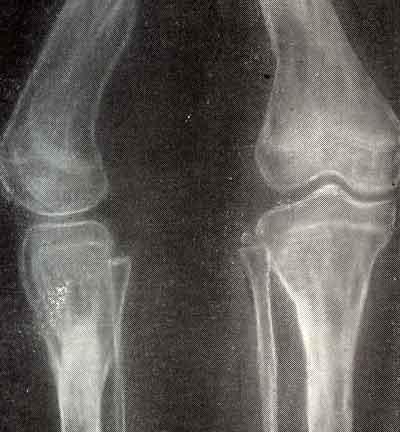

Вальгусная деформация голени на почве дисхондроплазии у ребенка 12 лет вид: до операции, результат после выскабливания патологического очага, остеотомии и гомопластики и результат через 2 года.